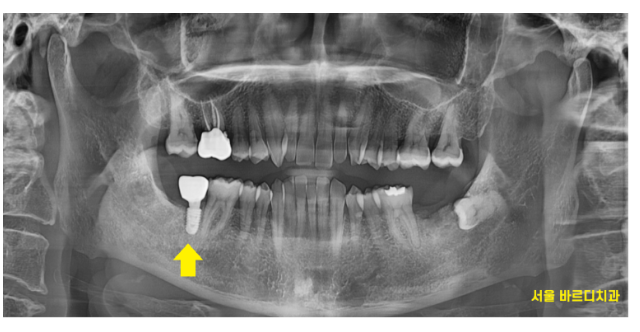

240217

3개월정도 지나 임플란트가 뼈와 단단히 고정되었을 때

머리를 만드는 작업을 진행하였습니다

역시나 디지털 방식인 구강 스캐너를 사용하여

보철을 예측하여 제작

240307

씹을 수 있게 제작해드렸습니다.